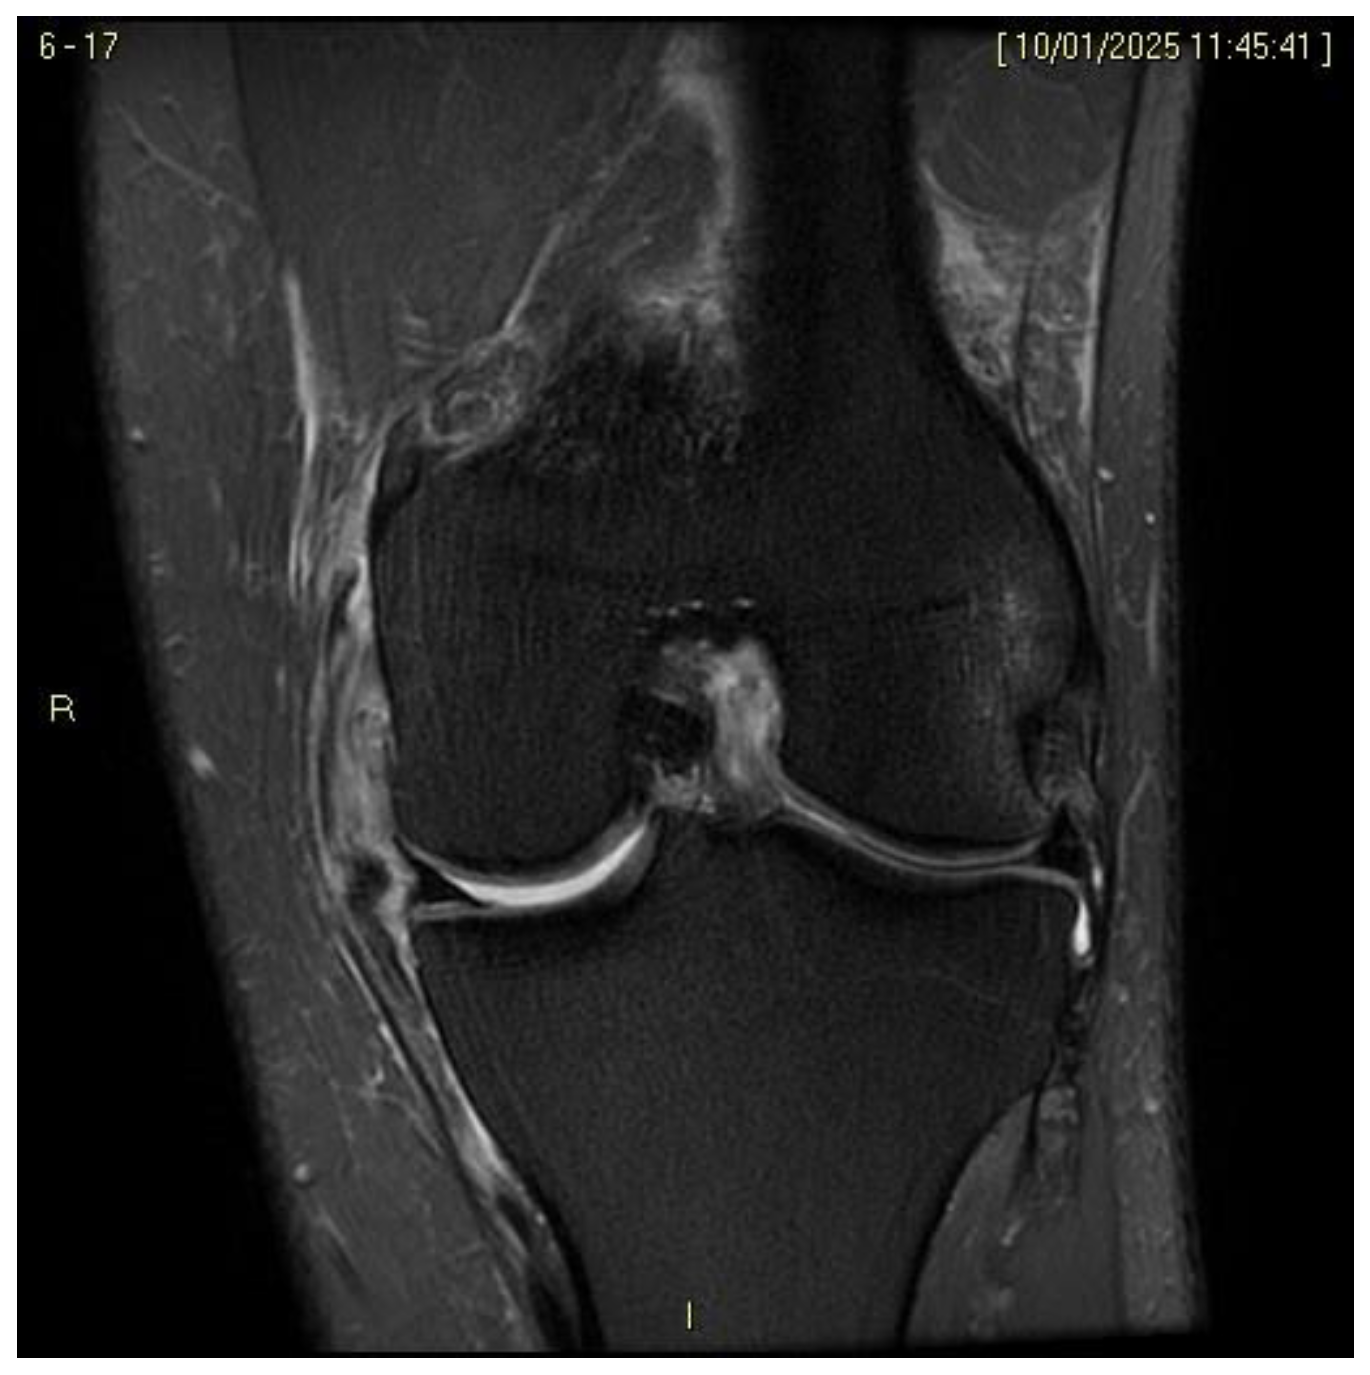

4.4. Magnetic Resonance Imaging (MRI) in the Diagnosis of ACL and MCL Injuries